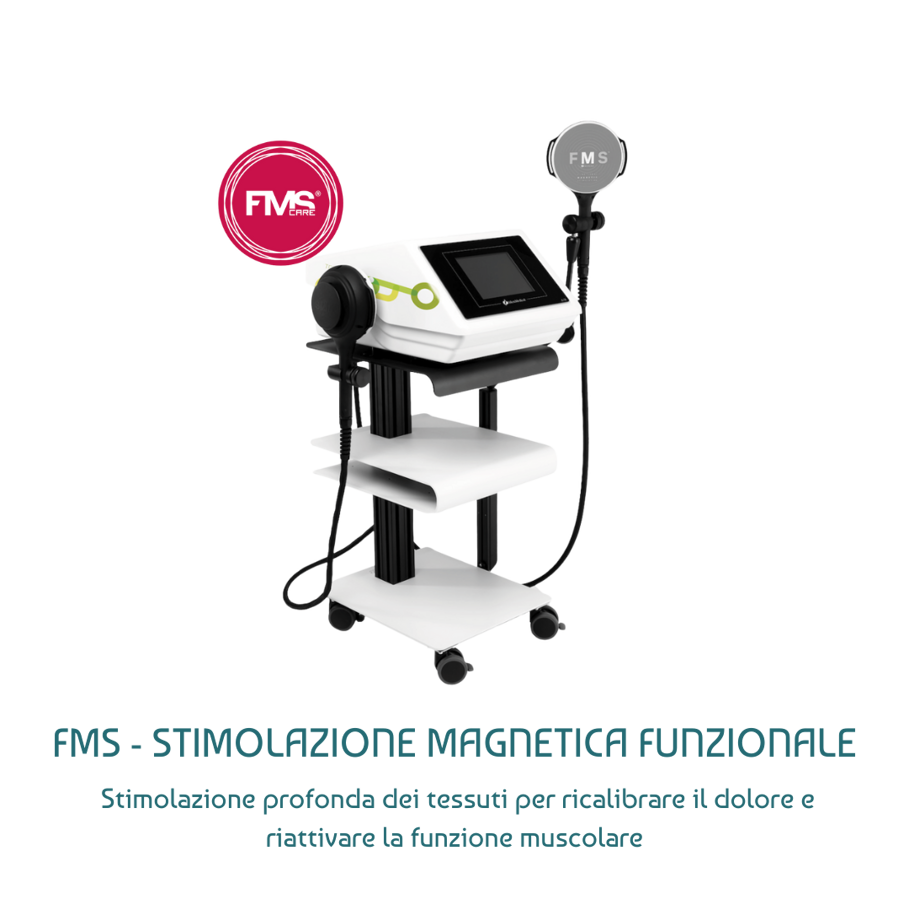

TECNOLOGIE AL SERVIZIO DELLA BIOLOGIA

Utilizzo strumenti d'elite per modulare i processi biologici e creare l'ambiente ideale per la guarigione del tessuto.